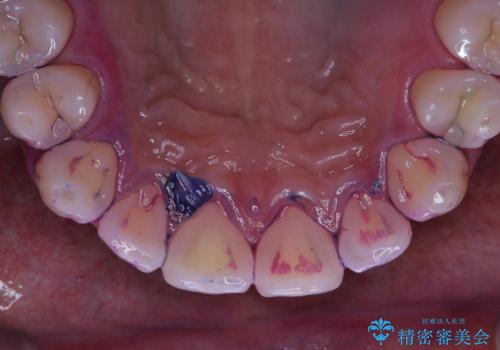

歯垢染色液を使うと、一見きれいな歯でも染まっている所が全て歯垢(プラーク)なのがはっきり分かります。歯に付着した歯垢(プラーク)は肉眼では認識しにくいものです。完璧に磨けているつもりでも、磨き残しが残っているかもしれません。

毎日の歯磨きだけでは、隅々までキレイに磨くことは困難です。さらに、体調不良や疲労などで免疫が低下しているとお口の中の細菌が増えやくなることがあります。